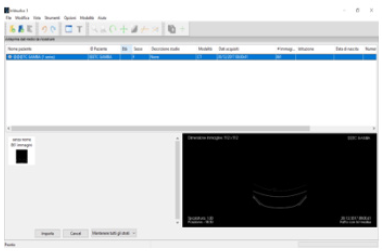

The methodology proposed in this paper uses tomographic images as a starting point for generate a three-dimensional model. Thanks to this technique, the density of tissues crossed by X-rays is converted into different gray levels. The program in Vesalius was chosen for this purpose as in it is a free medical software. It is able to generate virtual reconstructions of structures of human body based on CT scans. The first operation to be performed in in Vesalius is importing a DICOM format file (Figure 7)[8].

Following the import, the software allows to visualize the biological structure of interest in the three main axes of the human body (Figure 8)[10]. The next step is to segment the image using a colored mask. The mask is nothing but gray threshold level comparable to a certain tissue density. By setting the density range, the software highlights a specific region and creates its three-dimensional model, eliminating the rest. There is the possibility of pre-defined range (for example: compact bone, spongy bone, skin, muscular tissue etc.) or it can be changed manually. After the correct identification of the mask, the 3D surface is generated using the proper command (Figure 9). In the analyzed case it was preferred to use the “ Compact bone (adult) “ because the range was more limited avoiding other possible tissue inclusion. When the mask covers the right areas, the creation of the three-dimensional surface is performed. This is displayed in the lower right window (Figure 10). Once the 3D surface is created and exported in STL format for further modifications. Generally, the mesh created by In Vesalius is coarse and not homogeneous, so it needs an optimization process.